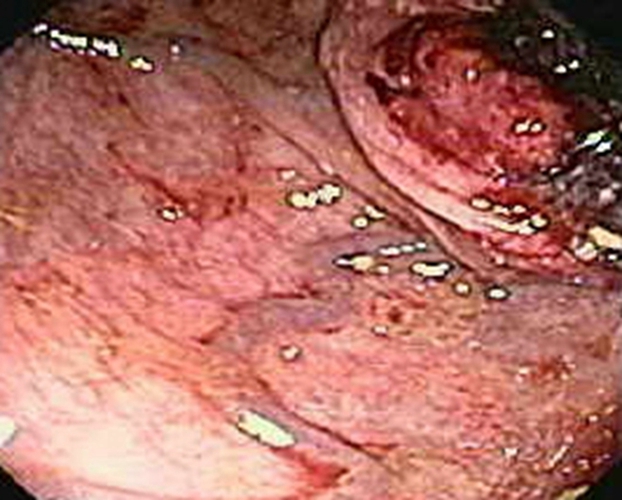

右半結腸癌潰瘍型常見臨床 特點

乙狀結腸癌潰瘍型症狀